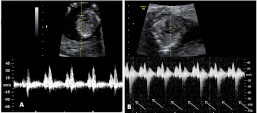

La ecografía en 4D (vídeo) no deja lugar a dudas. Se trata de un embarazo de siameses de 11 semanas de gestación, que están unidos por la zona abdominal, ya que comparten una pequeña parte de hígado. La movilidad de los bebés es reducida, como vemos en las imágenes, debido a la unión de sus cuerpos. Uno de los hermanos (el de la derecha) mueve la cabeza hacia atrás, mientras las piernas se entrecruzan. Los especialistas siguen este tipo gestaciones muy de cerca y valoran la separación quirúrgica de los bebés, una vez que se produce el parto.